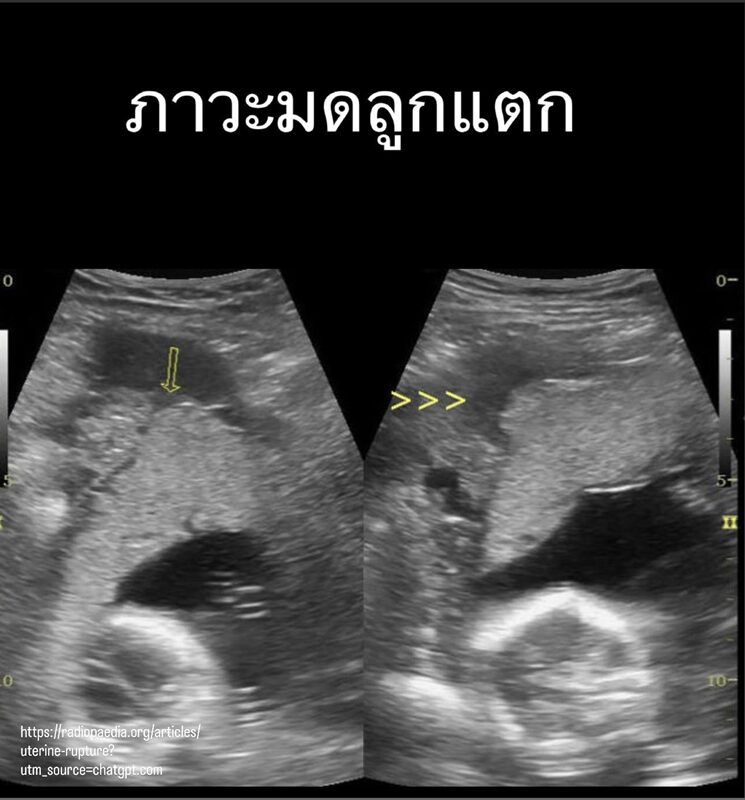

ภาวะมดลูกแตก (Uterine Rupture) เป็นหนึ่งในภาวะฉุกเฉินทางสูติกรรมที่แพทย์กังวลมากที่สุด แม้จะพบไม่บ่อย แต่หากเกิดขึ้นแล้ว ความรุนแรงอาจเกิดขึ้นอย่างรวดเร็ว และอาจเป็นอันตรายต่อทั้งคุณแม่และทารกในครรภ์ได้ในเวลาอันสั้น

ภาวะนี้คือการที่ผนังมดลูกฉีกขาดทะลุครบทุกชั้น ทำให้ทารกอาจหลุดออกจากโพรงมดลูกเข้าไปอยู่ในช่องท้องของมารดา ซึ่งถือเป็นสถานการณ์วิกฤตที่ต้องได้รับการผ่าตัดช่วยเหลือทันที